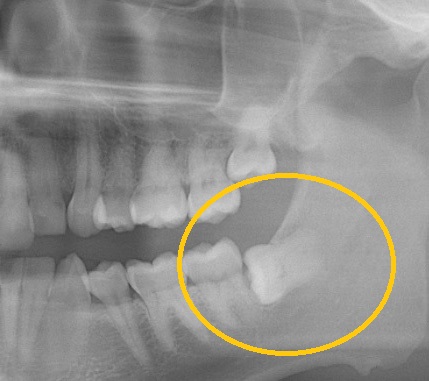

Our clinic has got some of the best and qualified surgical doctors for simple and complex teeth extractions. The treatment involves a procedural approach. After looking at the X-ray and examining your mouth, the dentist will inform you which approach is most likely and the anticipated cost of the extraction. Bear in mind, that sometimes, it is not until the doctor makes a start to the procedure in order to know the exact approach that is going to be necessary, and should the tooth awkwardly fracture when attempting a simple extraction, we might need to progress to a sectional or surgical extraction to remove it. Some common cases include broken tooth with complications.

The removal of impacted wisdom teeth involves a minor surgical operation. Although uncomplicated wisdom tooth surgery may be carried out under local anaesthesia, in many cases it is more appropriate for the patient to have a full general anaesthetic, which would be undertaken as day surgery. The process is absolutely painless.